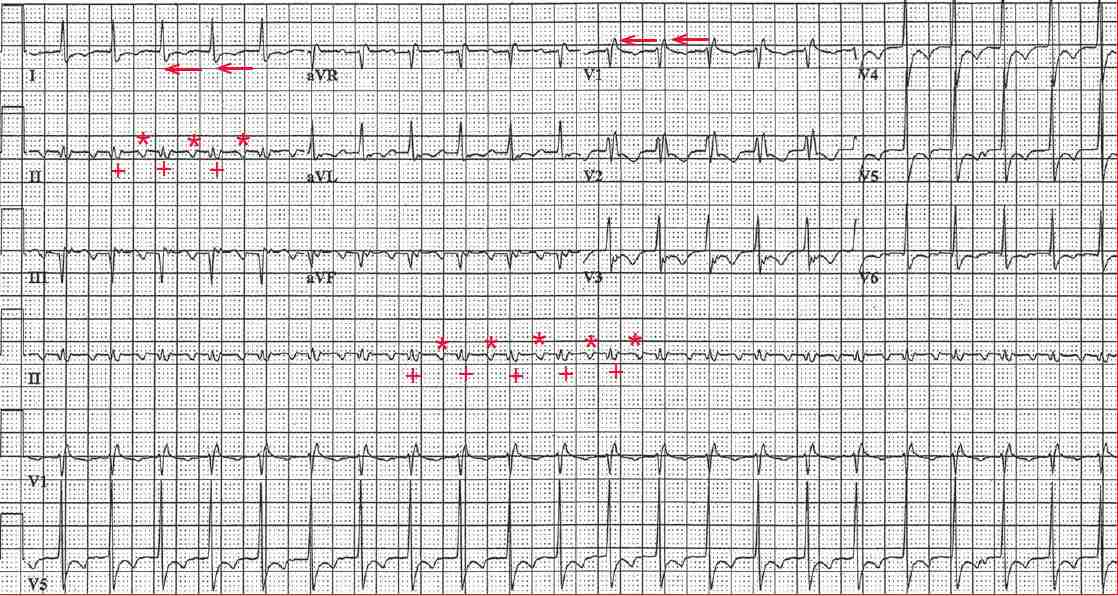

There is a regular rhythm at a rate of 140 bpm. The QRS complex duration is increased (0.12 sec). There is an RSR′ morphology in lead V1 (←) and an S wave in leads I and V4-V6 (←), diagnostic for a right bundle branch block (RBBB).

Negative atrial waveforms can be seen in leads II and aVF (*). A second atrial waveform (+) is seen at the end of the QRS complex, particularly in lead II. Although it looks like an S wave, it has the same morphology as the atrial waveform that is seen before the QRS complex and the interval between the two atrial waveforms is the same and stable, at a rate of 280 bpm.

The regular atrial rate of 280 bpm is diagnostic for atrial flutter, and there is 2:1 AV conduction. Atrial flutter is often a difficult rhythm to diagnose because one of the two flutter waves may be within the QRS complex, at the end of the QRS complex (resembling an S wave or even ST-segment depression), or at the beginning of the QRS complex (suggesting a Q wave).